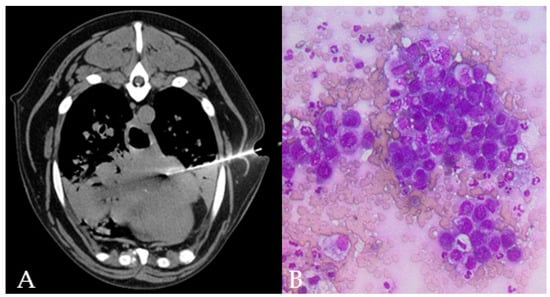

Figure 3.

TC-guided FNAB in the accessory lung lobe of the right lung of a 15 year old, male Mix breed dog, is visible through the left thoracic wall (A). Lung collapse/infiltration of the ventral part of the cranial lung lobes is present. Cytology (B) shows clusters of epithelial cells with moderate pleomorphism and anisokaryosis, round nuclei eccentrically placed with multiple nucleoli and deeply basophilic cytoplasm with punctate vacuolations in a dog with final diagnosis of lung metastatic carcinoma.